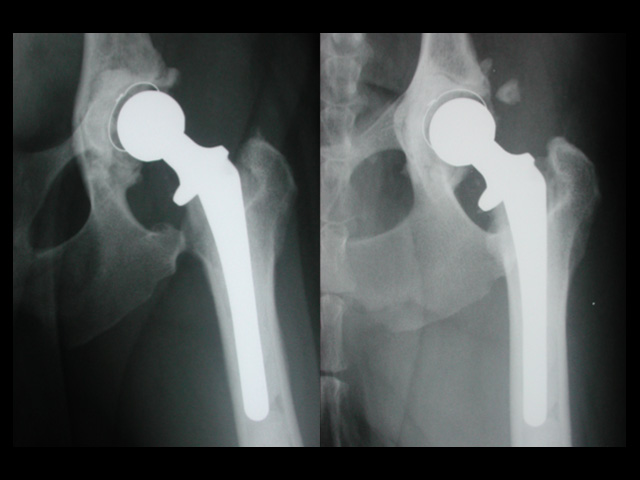

股関節形成不全Hip Displasia ゴールデンレトリーバー2歳オス CFX L:手術直後 R:8年 バーニーズマウンテンドッグ14ヶ月齢 BFX 手術3ヶ月後 イヌの股関節形成不全は、股関節の緩みや関節炎の原因となる遺伝的疾患です。正常な股関節は、骨盤側の寛骨臼と大腿骨側の大腿骨頭とがしっかりと連結した球状関節を形成しますが、股関節形成不全の場合ではこの連結は次第に緩み、部分的変位または亜脱臼を示すようになります。亜脱臼は、後に関節炎や形成異常の原因となります。 イヌ股関節形成不全症の発生には未だに不明な点が多く、遺伝、過剰栄養、エストロゲンの代謝不均衡、運動性の向上などの環境因子が影響しているといわれている。また、動物の急速な成長は股関節コンポーネントの不均衡をもたらし、運動性の増加は未熟な関節に対して過剰なストレスを加え続ける結果となります。 股関節形成不全の治療は、症状や関節変性の強弱により異なります。X線検査で構造異常が偶然見つかった場合でも、明らかな症状が見られない場合には治療の対象にはなりません。症状が軽度の場合には、犬用の非ステロオイド性抗炎症剤(NSAIDs)の投与が有効な場合があります。成長期にあって関節の緩みがあり、かつ変性が見られない場合には、寛骨臼の被覆角度を大きくする骨盤三点/ニ点骨切り術(TPO/DPO)が適応となり、それ以外では股関節全置換術(THR)が最良の治療方法となります。痛みを解消する目的で大腿骨頭を切除する大腿骨頭骨頚切除術(FHO)は、特に大型犬では荷重関節の消失による跛行をもたらすため、非常時の救済的手術法として位置付けられています。 椎間板ヘルニア/その他 股関節脱臼